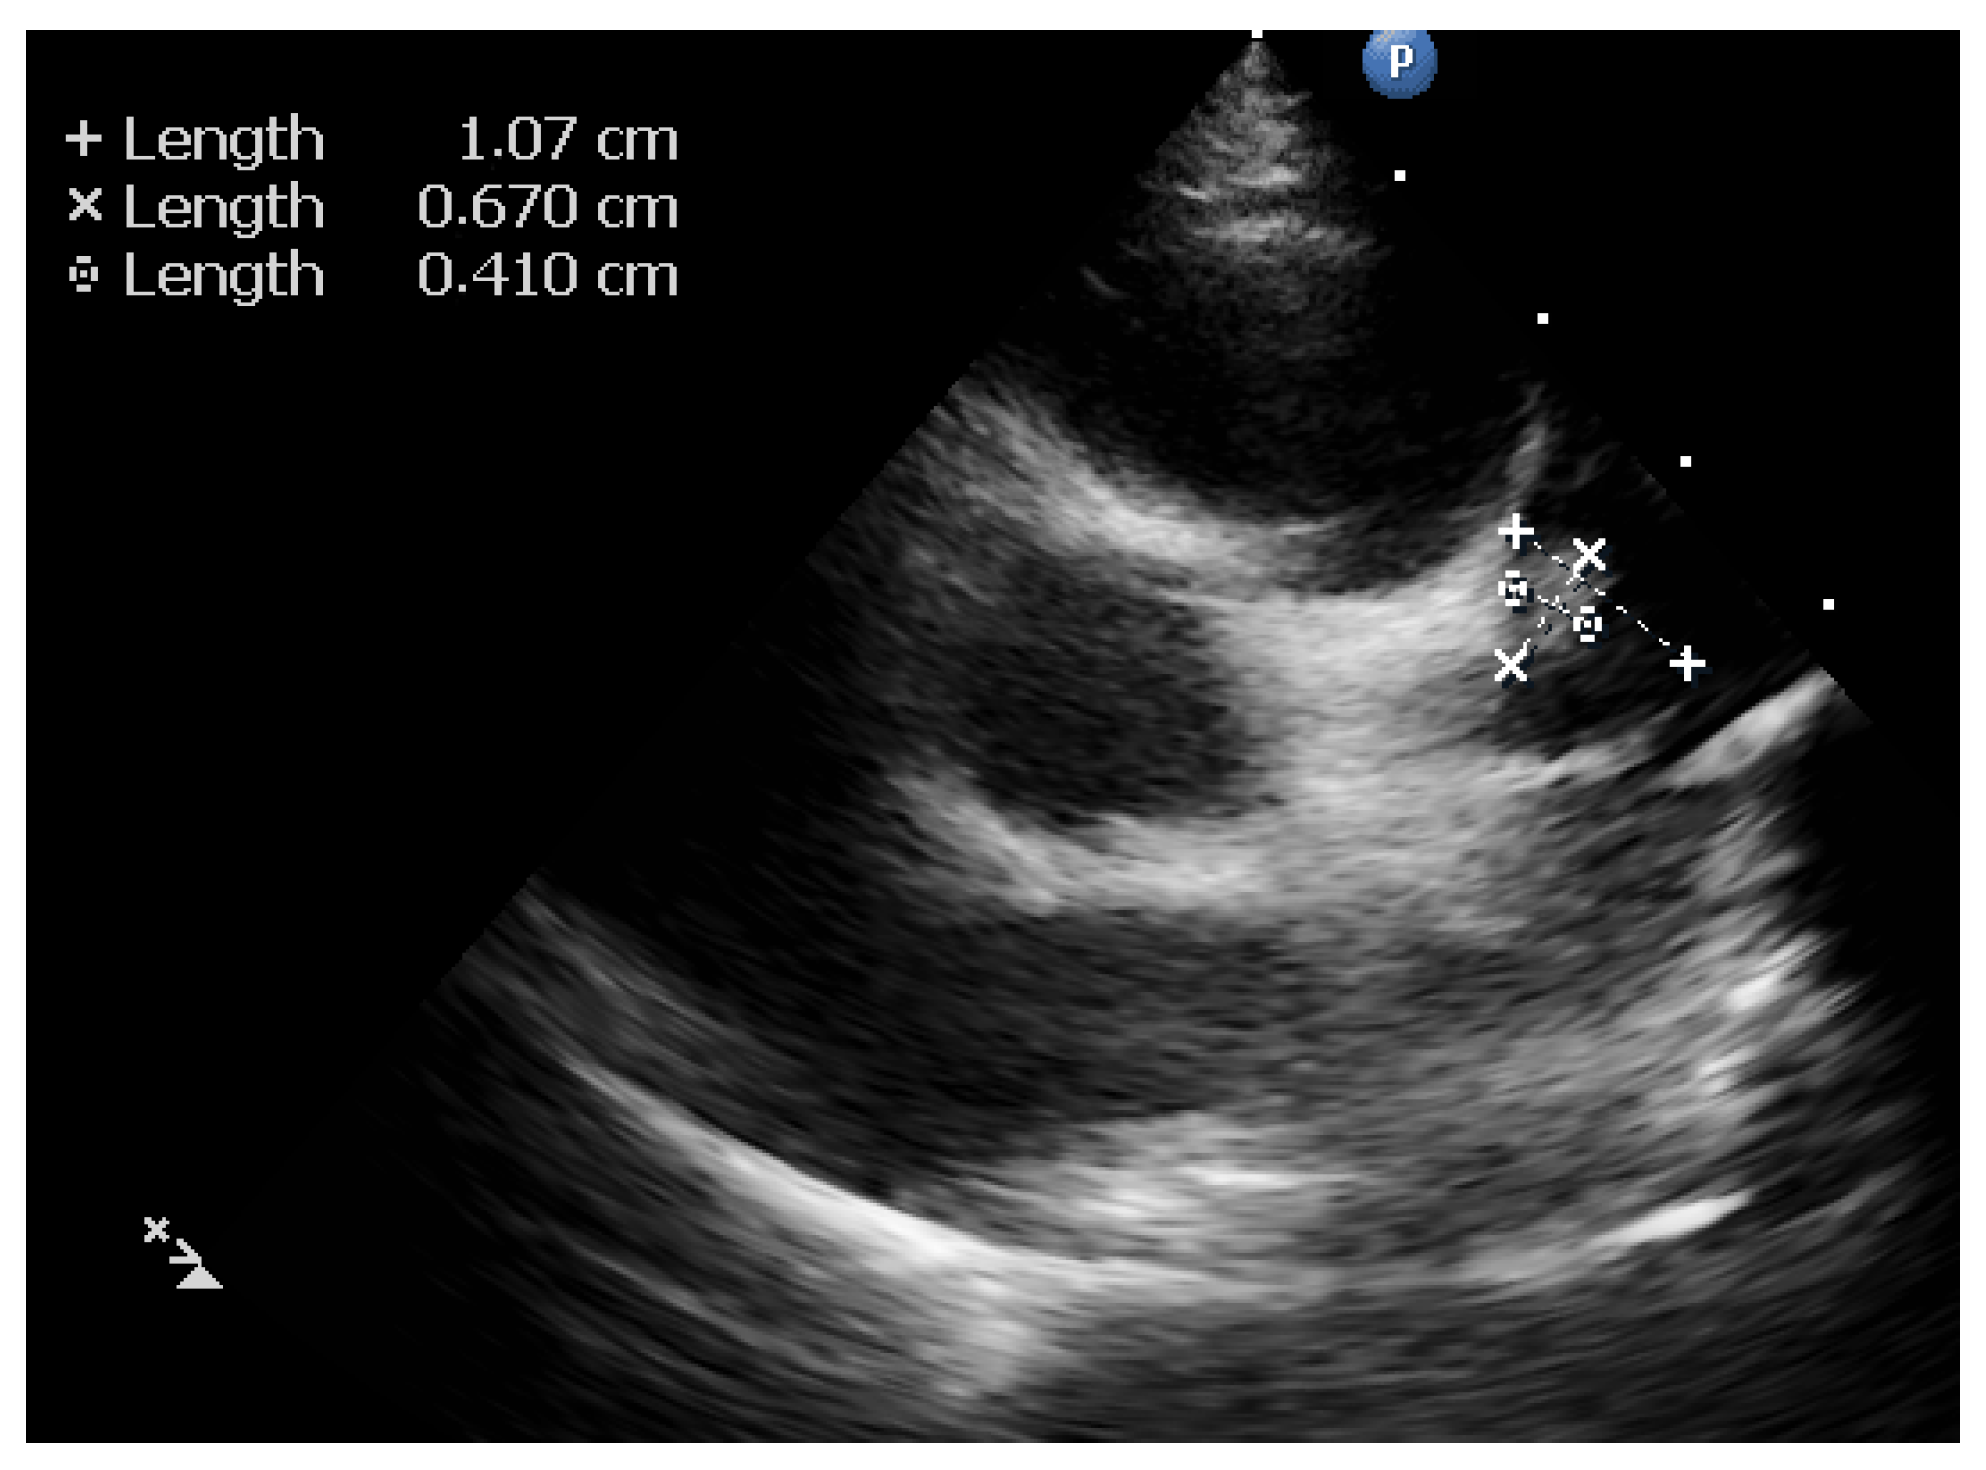

2. Case Report